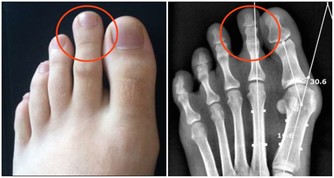

痛風症狀

痛風石中老年人比較常見的疾病之一,男性患者比較多,往往夜間突然發病,局部關節紅腫、疼痛劇烈,皮膚會呈青紫色、發亮,有明顯的壓痛感以及局部隆起現象,有時關節還會有活動障礙現象的發生。